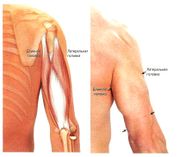

| 04:29, 14 июля 2016 | Mishci sport34.jpg (файл) |  |

72 КБ | Anes | Плечевая мышца | 1 |